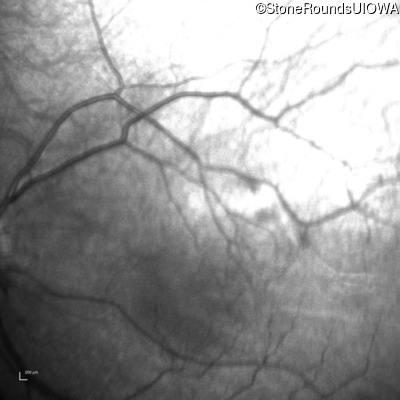

Infrared Fundus Photograph - Left - 20/80

Exemplar